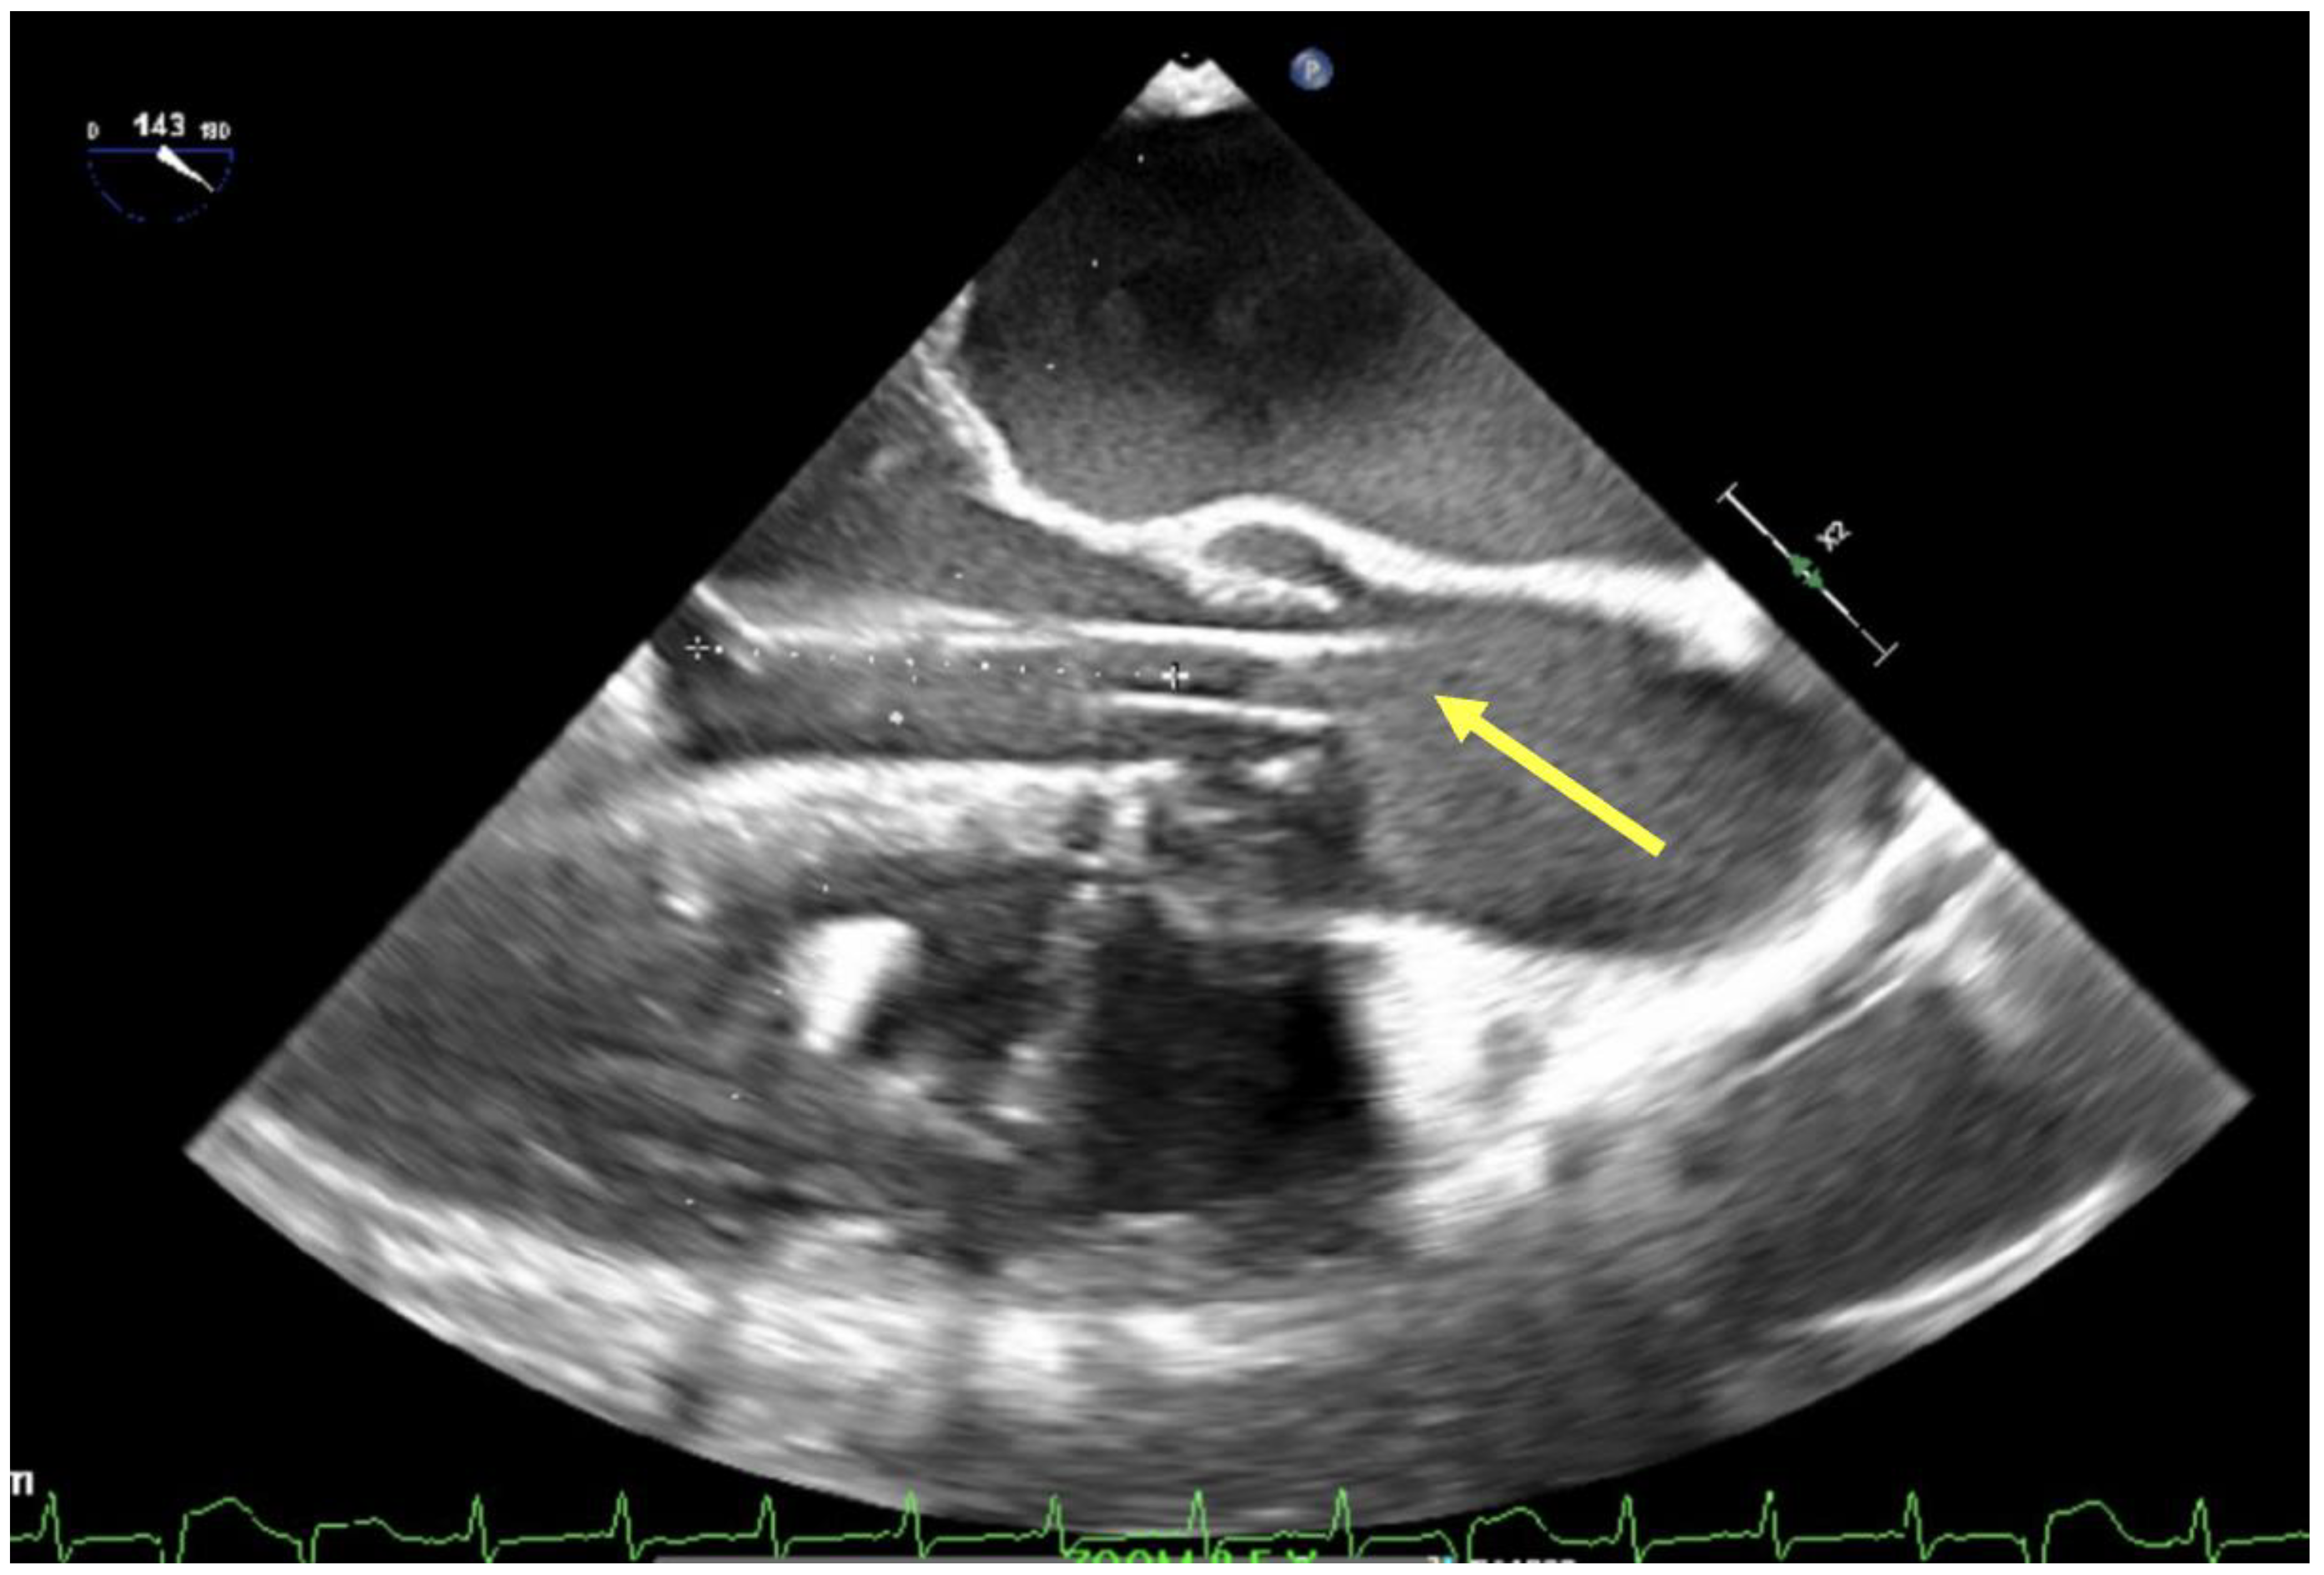

- Klopman, M.A.; Chen, E.P.; Sniecinski, R.M. Positioning an intraaortic balloon pump using intraoperative transesophageal echocardiogram guidance. Obstet. Anesth. Dig. 2011, 113, 40–43. [Google Scholar] [CrossRef]

- Crowley, J.; Cronin, B.; Essandoh, M.; D’Alessandro, D.; Shelton, K.; Dalia, A.A. transesophageal echocardiography for impella placement and management. J. Cardiothorac. Vasc. Anesth. 2019, 33, 2663–2668. [Google Scholar] [CrossRef] [PubMed]